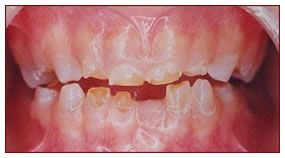

Composite Filling

Teeth affected by decay or trauma are restored with tooth coloured composite material.

Composite Filling with Strip Crown